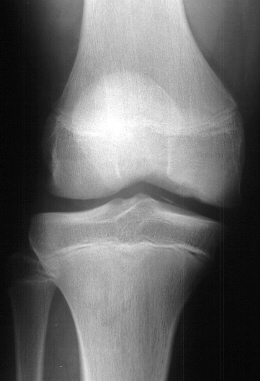

with a mildly positive apprehension test. Based on the radiographs

and his clinical exam an arthroscopic examination was performed.

At arthroscopy the medial femoral condylar defect was not apparent,

but a large retinacular tear was discovered. Also, the patient

had an osteochondral fracture of the lateral femoral condyle and

a free 7 mm by 5 mm intraarticular cartilage fragment.